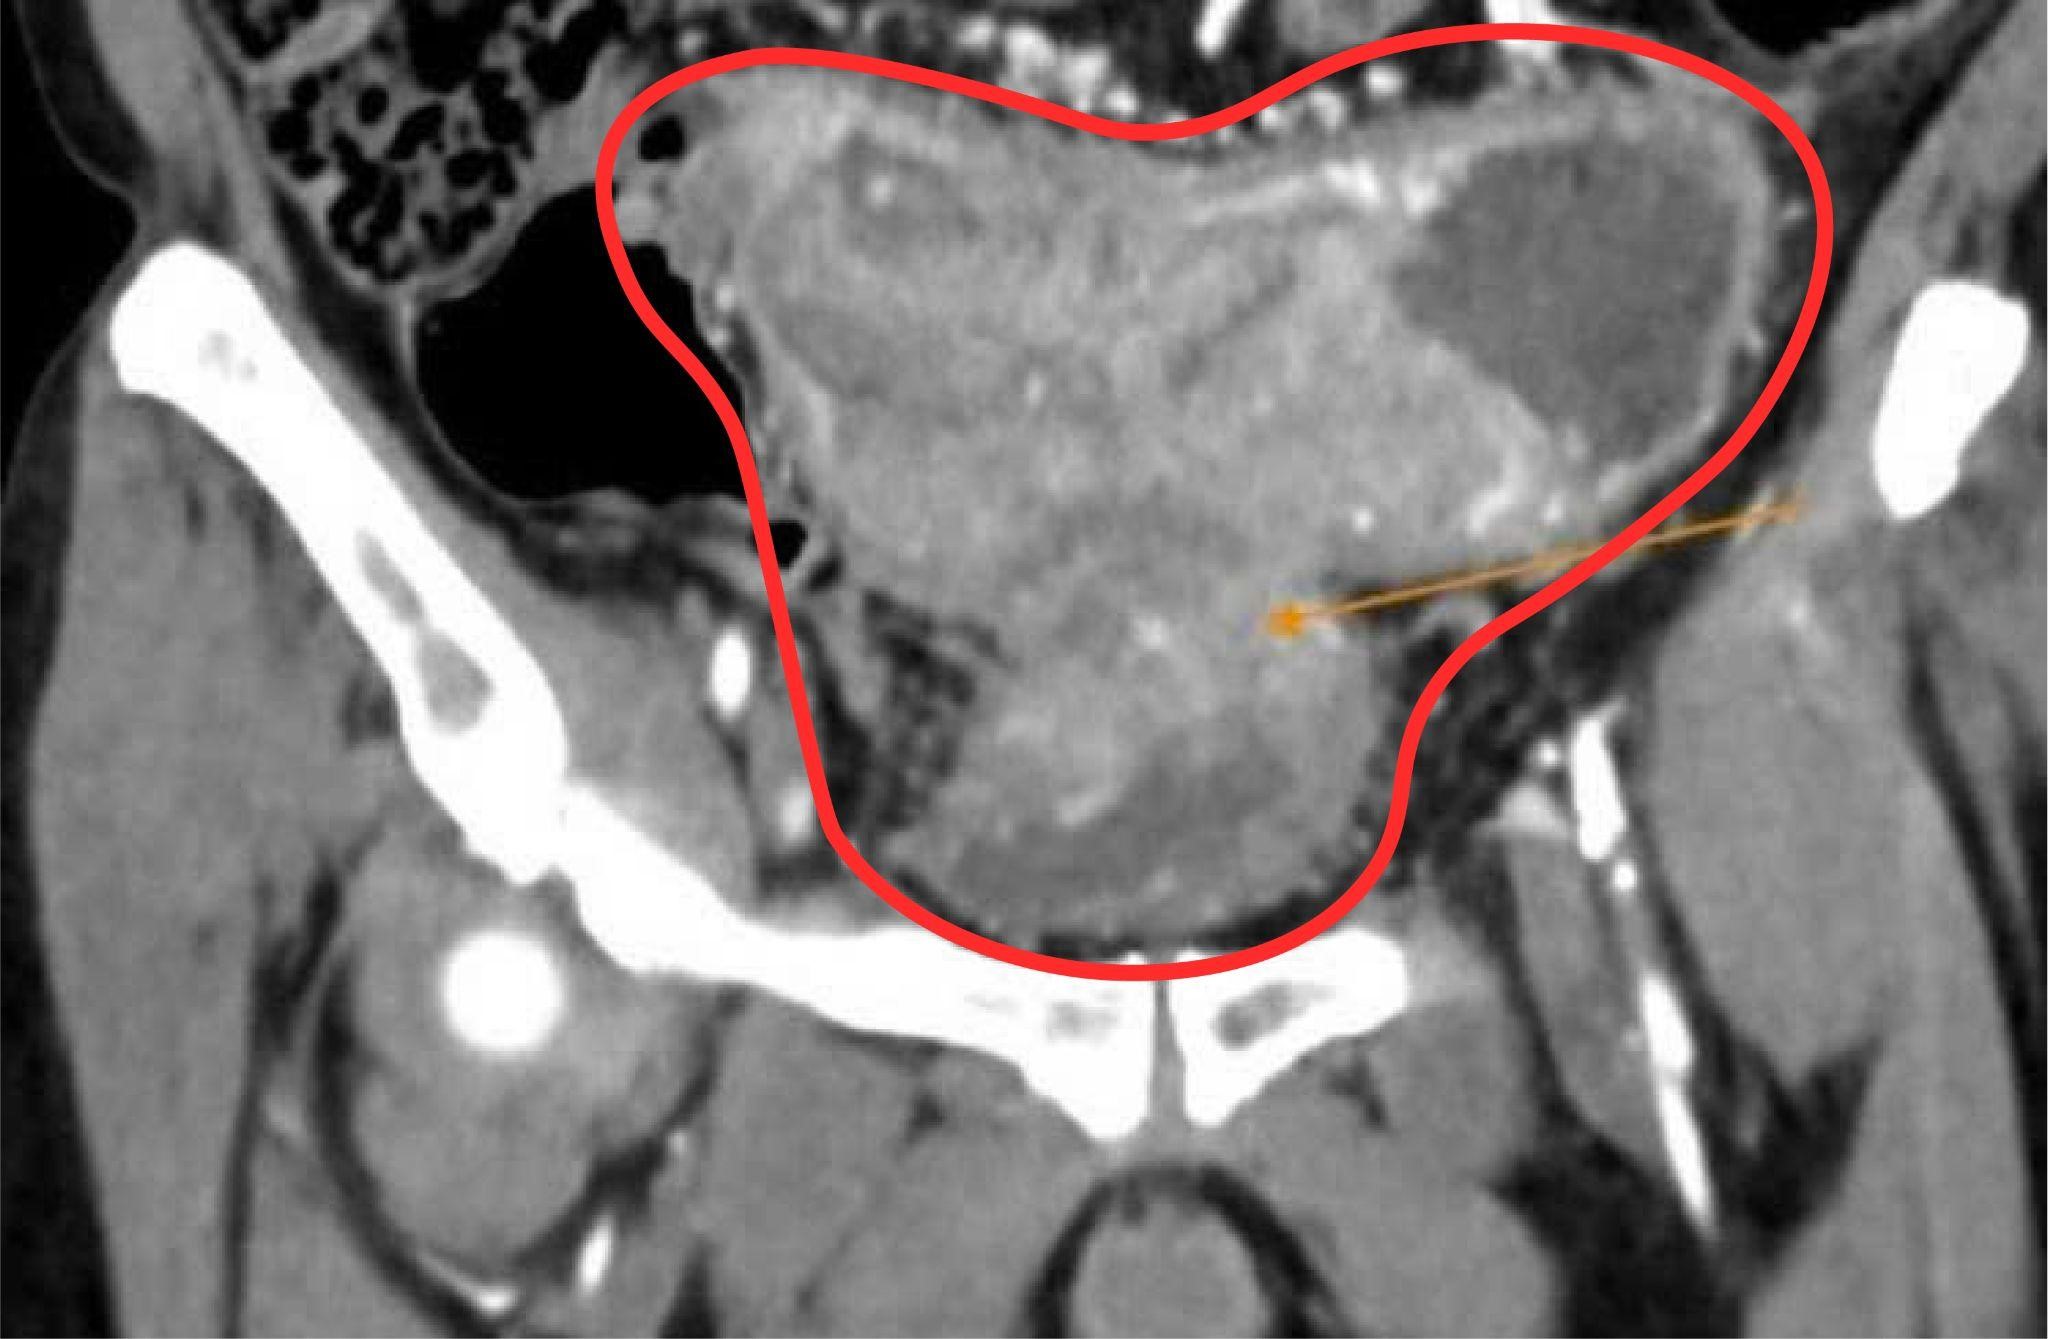

He returned home and began taking traditional medicine, consuming three bowls of decoction daily and avoiding meat. His constipation worsened, he lost 15 kg, struggled to eat and drink, and experienced abdominal pain and bloating. Six months later, he returned to the hospital. An abdominal CT scan revealed a malignant tumor completely narrowing the bowel lumen, leading to fecal impaction and bladder wall thickening. His liver showed two lesions from metastatic colon cancer.

Scan images show a malignant tumor narrowing the bowel lumen and thickening the patient's bladder wall. Photo: Tam Anh General Hospital